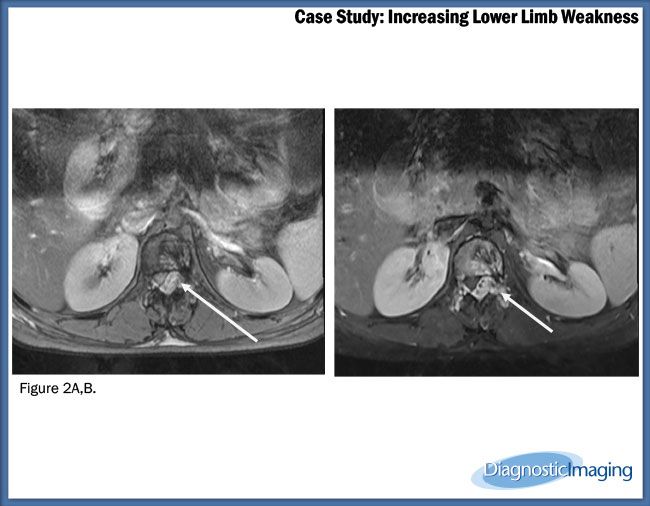

Case History: 22-year-old female with bilateral lower limb weakness for 25 days.

Case History: 22-year-old female presented with bilateral lower limb weakness for last 25 days. Weakness gradually increased with time.